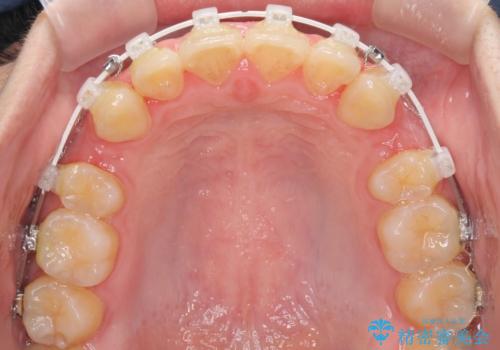

- 審美装置

- 2年3ヶ月

- 10-30回

口元を下げて口唇を閉じやすくする場合、抜歯矯正をお勧めさせていただくことが多いです。